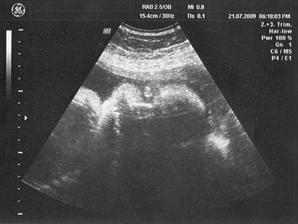

21/7 09 PORADNA 31 + 2 tt - Mája překvapila, místo obvyklé aktivity jen zívala a třela si očička, asi se ukládala ke spánku, takže důkaz že taky někdy spí, doteď sem o tom zatím pochybovala 🙂) ... placenta je opět ok /musím zaklepat/ a máme další fotky do sbírky